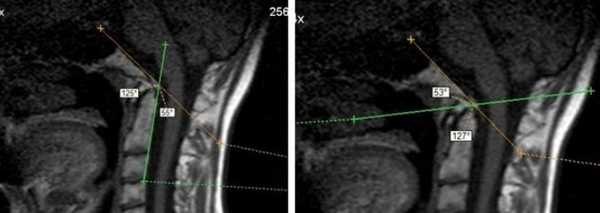

МРТ краниовертебрального перехода. Краниовертебральный угол уменьшен до 125 гр. Угол Богарта увеличен до 127 гр. Зубовидный отросток С2 позвонка расположен на уровне линии Чемберлена. Признаки диспластических изменений краниовертебрального перехода — платибазия.

Платибазия

Достаточно частая аномалия, характеризующаяся уплощением основания черепа. Может быть врожденной или приобретенной в результате рахита, остеопороза, длительной внутричерепной гипертензии в раннем возрасте и других причин.

Платибазия I и II степени определяется только на МРТ и может не иметь клинических проявлений. При III степени уменьшается объем задней черепной ямки и появляются неврологические симптомы:

Базилярная импрессия

Часто сочетается с платибазией. Это выпячивание зубовидного отростка аксиса в большое затылочное отверстие, что приводит к сдавлению нервов, сосудов, нарушению оттока спинномозговой жидкости. Проявляться может только к 15 − 25 годам.

На МРТ краниовертебрального перехода − платибазия и базилярная импрессия при несовершенном остеогенезе